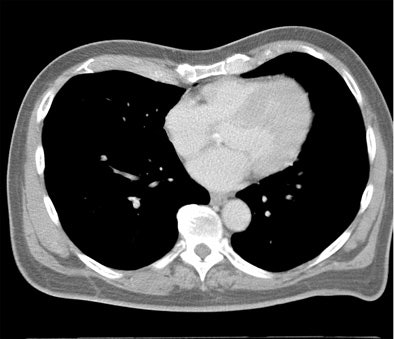

From there, expanding the FOV to the entire thorax for screening of other important findings (lung, breast, axilla, mediastinum, and spine) would actually boost the radiation dose by 67.5%, he said.

The heart fits in a 25-cm field-of-view, permitting the use of a small bowtie filter in medium-sized and sometimes even larger patients, Budoff said. "We're only worried about the heart," he said.

The results of Kim et al in Radiology (May 2010, Vol. 255:2, pp. 369-376) offer a striking picture of just how rare significant lung findings are, he said.

The study involved the acquisition of full thoracic images that were read twice: once in the full version and once in a limited field-of-view. Among 11,654 patients, the investigators found 36 cancers on full thoracic scans or about three cancers per 1,000 patients scanned. The mean diameter was 23 mm, and just 16 of 36 cancers were stage IA cancers, the most curable kind. As for the rest, half of the patients with advanced cancer died within 20 months, Budoff said.

- On cardiac large FOV = 19 cancers were visible (0.16%)

- On cardiac small FOV = 4 cancers were visible (0.03%)

Looking at the small field-of-view meant missing some cancers, Budoff said, but in light of the fact that only 16 cancers were resectable, and that many of the patients died despite having undergone a full apex-to-base thoracic CT scan, the small field-of-view didn't miss much, Budoff said.